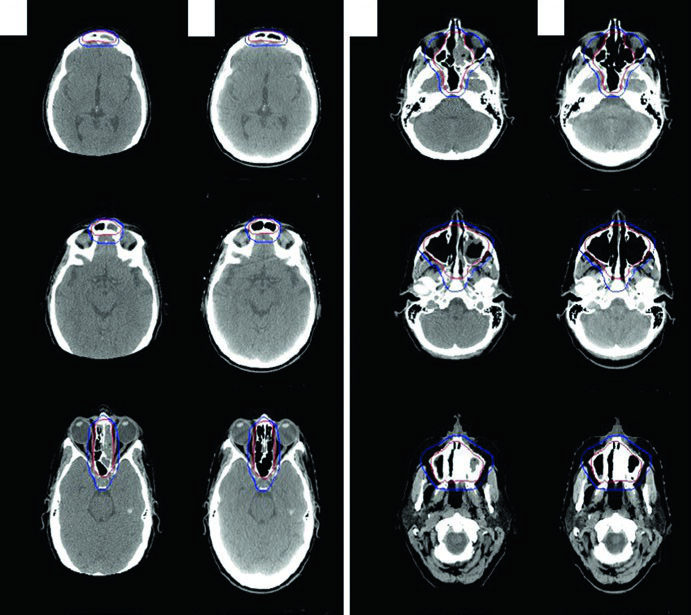

Linfoma Orbital e Sinonasal

A simulação é feita em decúbito dorsal, braços ao lado do corpo e imobilização com máscara termoplástica. Para linfoma orbital, as opções técnicas incluem par de cunhas superior-inferior, 3DCRT ou IMRT. Bolus pode aumentar a dose superficial em doença localizada de tecidos moles. Quando a dose prescrita alcança 30 Gy ou mais, considerar blindagem da glândula lacrimal.

Em doença indolente limitada da conjuntiva, o tratamento com feixe de elétrons anterior ou energia mista elétrons/fótons é uma alternativa, com blindagem do cristalino se o tumor estiver na periferia. Para linfomas sinonasais, 3DCRT ou IMRT é recomendada pelas doses mais altas necessárias e pela proximidade de estruturas críticas.

O caso ilustrativo é uma mulher de 56 anos com DLBCL de seio etmoide/esfenoide esquerdo, com extensão para a cavidade nasal direita cruzando o septo, erosão da placa cribriforme superiormente, erosão da parede orbital medial esquerda lateralmente e extensão para o seio maxilar esquerdo inferiormente. O seio frontal esquerdo estava completamente opacificado. Após ressecção quase total e 3 ciclos de R-CHOP, a RT consolidativa foi administrada com CTV ISRT cobrindo a totalidade dos seios envolvidos. A abordagem de delineamento de tumores da cavidade nasal e seios paranasais segue princípios semelhantes.